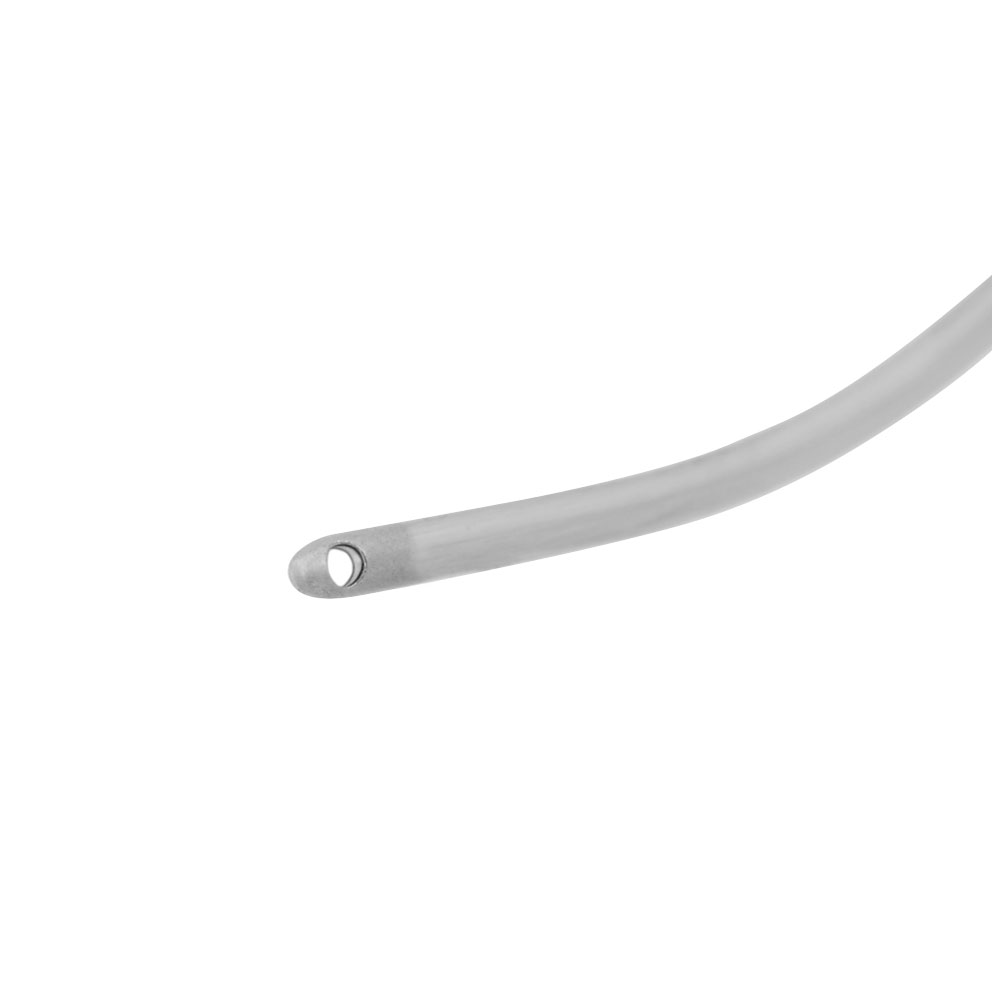

Irrigációs kézidarab PhacoVet készülékhez (329003), érdes kanüllel, 21G

- Aspiráláshoz és elszíváshoz

- Többször használható

- Érdes kanül

- 21G

- EICKEMEYER® PhacoVet készülékhez (329003)